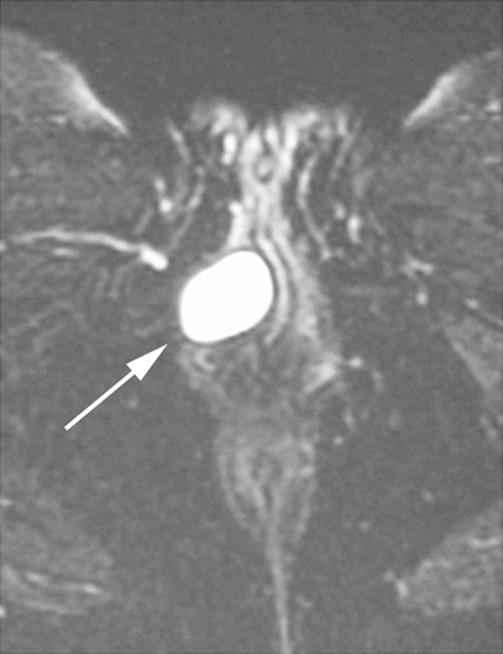

Fig. 8.2

Axial MRI showing a cystic lesion in the right labia. The cyst contains clear fluid (arrow)